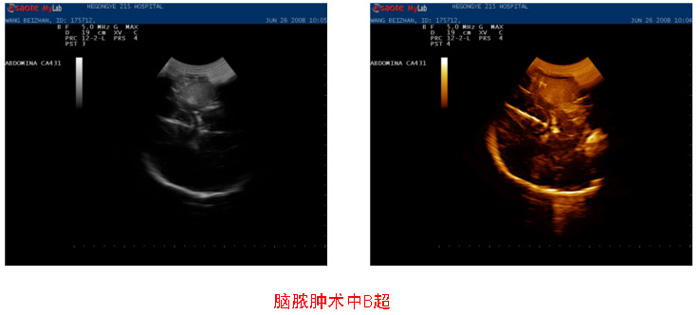

神经外科成功开展超声引导下微创手术治疗颅内深部肿瘤

超声引导是颅脑肿瘤微创手术的一种可行的方法,其定位准确,创伤小,可以提高肿瘤的全切率,为临床医生提供了有意义的指导。

颅内深部肿瘤术中能否准确定位是影响手术效果和减少并发症的关键,也是困扰神经外科医生的一个难题。2008年我院神经外一科与功能科程荣主任协作,应用术中B超定位成功解决了这一难题,全切除多例深部肿瘤,尤其是功能区深部肿瘤,术后无任何并发症。

采用日本ALOKA公司生产的B型超声仪PS-4000,颅脑专用防水微型探头(扇形凸阵和枪形探头),发射频率5MHz。将涂有耦合剂的探头包裹在一灭菌透明薄膜袋内,探头接触面与灭菌袋紧密贴敷。打开骨窗后,在硬脑膜表面进行纵切、横切或斜切扫查,确定肿瘤位置;打开硬脑膜后,再次在脑表面进行探测,了解肿瘤的大小、位置、距离表面皮质的距离及其与周围结构的关系。选择距离肿瘤最近、相对无功能区切开皮质切除肿瘤,术中随时进行B超检查以了解切除程度。手术切除完毕后,再次用B超检查确认无残留病灶,肿瘤全切除,然后常规关颅。

术中B超可以对肿瘤进行多个层面包括纵、横、斜等切面扫描,并且指导切除病变时的最佳入路,同时显示病变切除范围大小,做到最小的创伤得到最大范围的切除,符合微创理念。由于颅骨对超声穿透的阻碍,在开颅后阻碍消除,效果显著。近年来,随着B超图像质量的不断提高以及三维超声的出现,颅脑B超的使用范围不断扩大。术中B超具有诸多优点: (1)反复性和实时性:可在硬脑膜表面或脑组织表面反复操作,提供术中连续性图像信息。这是CT和MRI无法替代的;(2)精准性:不受脑组织飘移的影响,可精准、实时确定病变的部位、大小和深度,评价病变与周围脑组织的关系,随时检查是否残留病变,提高全切率;(3)使用方便,操作简便,有助于缩短手术时间;(4)设备价格较低廉,患者承担的费用较低,适合基层医院采用;(5)对人体无损伤。(6)超声频率5 MHz或更高频率探头可以发现皮层下小病灶,从而鉴别实质性肿瘤、囊肿和坏死;超声频率10 MHz,可以用来寻找残余肿瘤和侵袭性肿瘤。